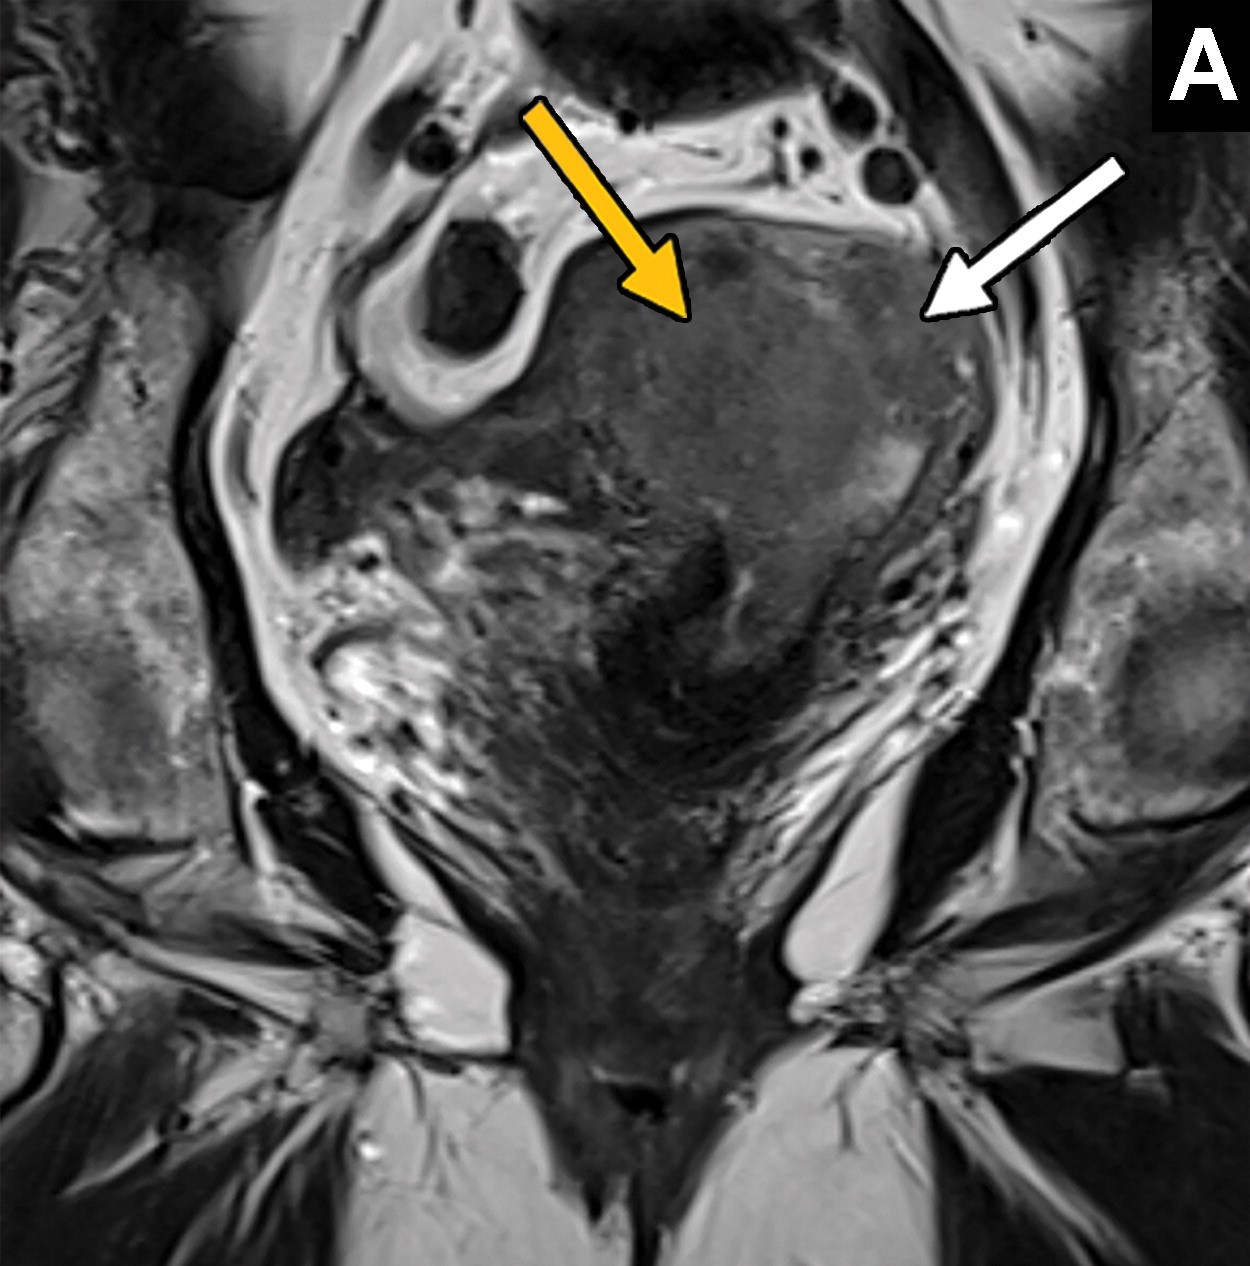

La RM se utiliza para evaluar el tamaño del tumor, la invasión miometrial y cervical, así como para determinar la extensión a órganos cercanos y ganglios linfáticos. La técnica combina secuencias T2 de alta resolución y difusión para una evaluación precisa. La invasión del estroma cervical y la afectación de ganglios linfáticos son factores importantes que influyen en el pronóstico.